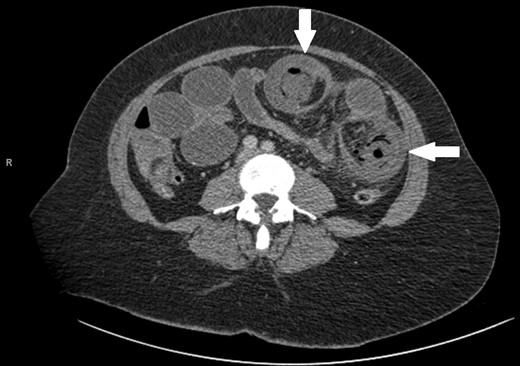

A 47-year-old female presented as an emergency with severe abdominal pain and profuse vomiting. She had been experiencing symptoms of intermittent vague abdominal pain associated with weight loss over 6 months, but no change in bowel habit. She had no significant past medical history. On examination she was tachycardiac, pyrexial and abdominal examination revealed distended abdomen with localized tenderness in the left iliac fossa. Blood tests revealed an elevated white cell count (18.8), C-reactive protein (25), microcytic anaemia (Hb 108) and a mildly raised lactate (2.37). She was commenced on intravenous fluids. An abdominal plain film showed prominent bowel loops and ultrasound of the abdomen revealed numerous loops of a distended, fluid filled, non-peristalsing bowel. There was some evidence of bowel wall thickening, but no clear source of obstruction was identified. A CT scan was performed showing mesenteric vascular gas and a target sign, virtually pathognomonic of intussuception [5, 6] (Figs 1 and 2).

While correct diagnosis is based on operative findings, suspicion may be raised following imaging techniques. CT with both oral and intravenous contrast is now widely recognized as the most accurate diagnostic tool (58–100% accuracy in a recent case series) [1, 4]. Alternating hyper- and hypodense layers of the bowel wall of the intussuscepted segment give rise to a classical ‘target sign’ [5] (Fig. 1).